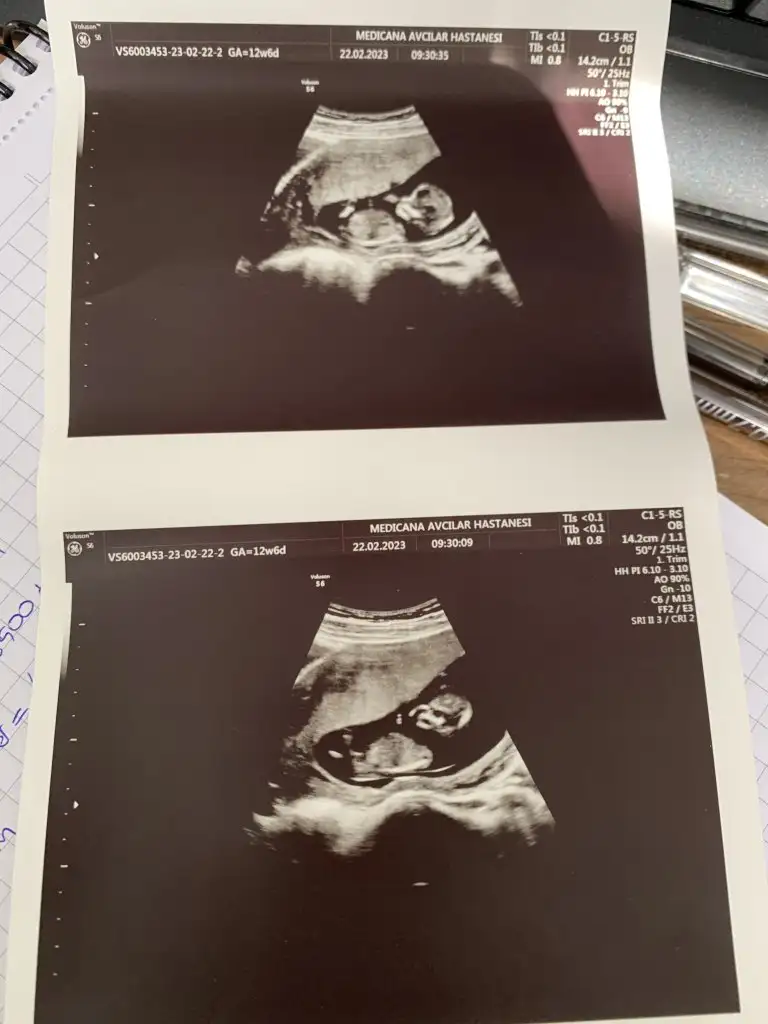

Merhaba arkadaşlar bu benim ilk hamileliğim o yüzden çok bilgim yok, bugün 12+4 de ikili ultrason yapıldı doktor cinsiyeti ne hissediyorsun dedi açıkçası içime herhangi bir şey doğmuyor yani kız yada erkek diye. Doktorum benim içime kız doğuyor haberin olsun dedi. Çok sevindim ama sonrasında kime söylesem hemen moda girme o sadece bi tahmin daha belli olmaz diyorlar. Erkek bebek kendini erken gösterir kızı 16. Haftaya kadar zor görüyorlar nasıl hemen söylemiş falan dedi yani şimdi kız dedi ama sonradan yanılma gibi bir payı var mı ? Çok mu erken cinsiyet için. Üstelik doktor çok sevindiğimi görünce yine de herkese söyleyip pembe şeyler alma hemen netleşsin , bana da bu zamanlar kız demişlerdi şimdi oğlum var dedi , ama 3 kez de üstüne basarak kız gibi görüyorum dedi. Açıkçası herkesin yorum yapması biraz böyle kafamı karıştırdı. Kız yada erkek asla farketmez sonuçta kızımda yok oğlumda ama insan ilk gebelik heyecanıyla bilip herkese söylemek istiyor sanırımböyle öğrenip sonradan cinsiyet değişen doktoru yanılan var mı ? Eskiler de çokmuş bu durum ama şimdi cihazlar çok gelişmiş olma diye umuyorum. Bu Arada fotoğrafta yüklüyorum belki sizde bi tahminde bulunursunuz

Nubu tam net gorunmuyo kapatmis ama kafa yapisi kiza benziyo yuvarlak kiz olma ihtimali yuksekBu foto 11haftalik cnm

Nubu tam net gorunmuyo kapatmis ama kafa yapisi kiza benziyo yuvarlak kiz olma ihtimali yuksek

Beklemekte fayda var bazi bebekler gostermiyo usg fotolari yaniltabiliyo cekme acisindangorunmiyor kucuk dedi